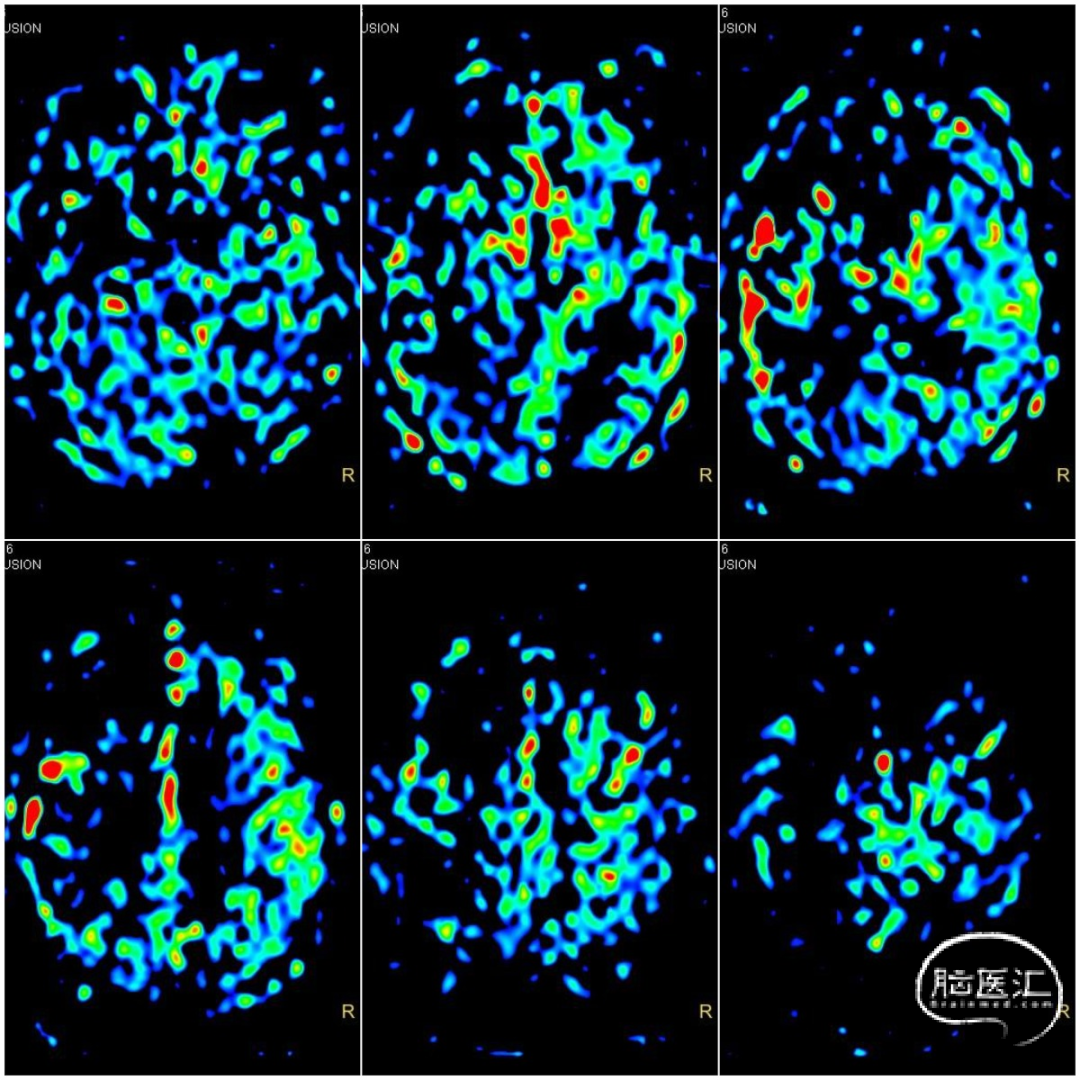

颅脑MRA+ASL提示右侧颈内动脉闭塞可能,大脑中动脉显影欠佳,伴低灌注。

术前病情分析:DSA提示右侧颈内动脉C1段末端以远闭塞,局部可见“杯口”征;经前后交通代偿供血。结合心电图提示房颤,病因分型考虑为心源性栓塞可能性大。